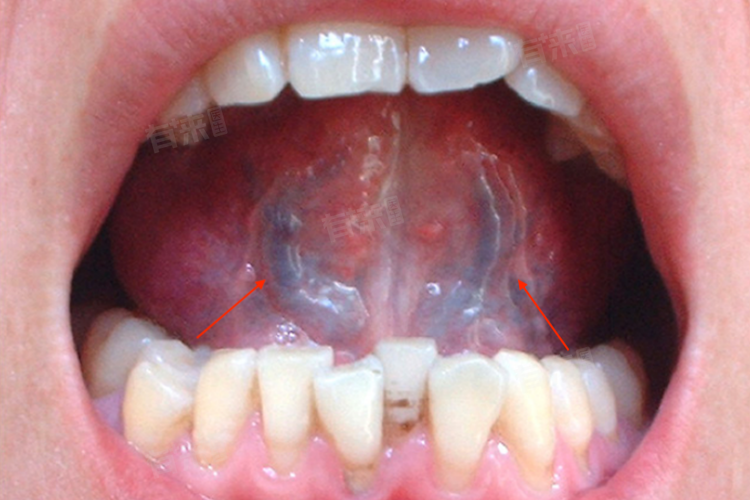

舌头底下血管(舌下络脉)发黑是中医舌诊的重要观察指标,可能提示气血运行异常或脏腑功能失调。其主要原因包括气滞血瘀、寒凝血瘀、热毒壅盛等。

1、气滞血瘀:情志不畅或久病致气机郁滞,血行不畅而瘀阻舌络。表现为舌下络脉青紫迂曲,伴有胸胁胀痛、月经色暗。治疗宜活血化瘀,方用血府逐瘀汤(桃仁、红花、当归等),配合针刺内关、太冲等穴。

2、寒凝血瘀:阳虚寒凝导致血脉收引,常见于老年或体寒者。舌下络脉紫暗,伴畏寒肢冷。当温经散寒,方选当归四逆汤(当归、桂枝、细辛等),艾灸关元、肾俞等穴。

3、热毒壅盛:外感热邪或饮食积热熏蒸舌络。舌下络脉紫黑肿胀,伴口干口苦。需清热解毒,方用黄连解毒汤(黄连、黄芩、黄柏等),配合少商、商阳穴点刺放血。

4、痰湿阻络:脾失健运致痰湿内生,阻滞舌络。舌下络脉暗紫粗胀,舌苔厚腻。治宜化痰通络,方选二陈汤合桃红四物汤(半夏、陈皮、桃仁等),配合丰隆、阴陵泉等穴针刺。